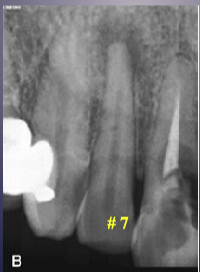

what is the black arrow pointing to

large sequestra caused by acute osteomyelitis